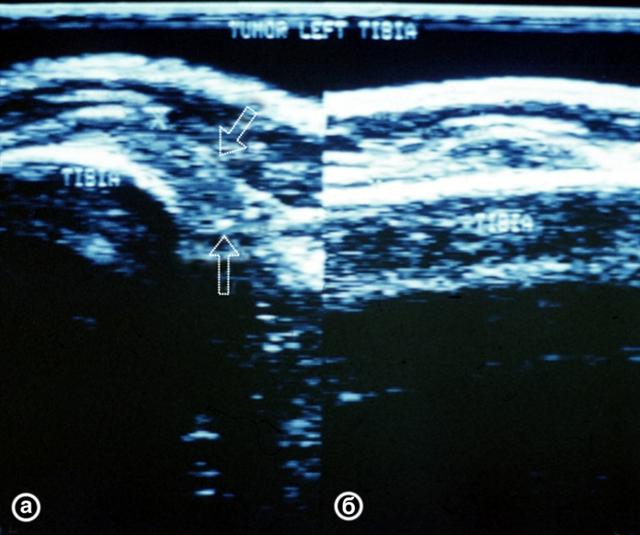

Рис. 28. Ультрасонограммы верхней трети левой голени (а — поперечная, б — продольная проекции) при околосуставной мягкотканной опухоли: опухоль указана стрелками.